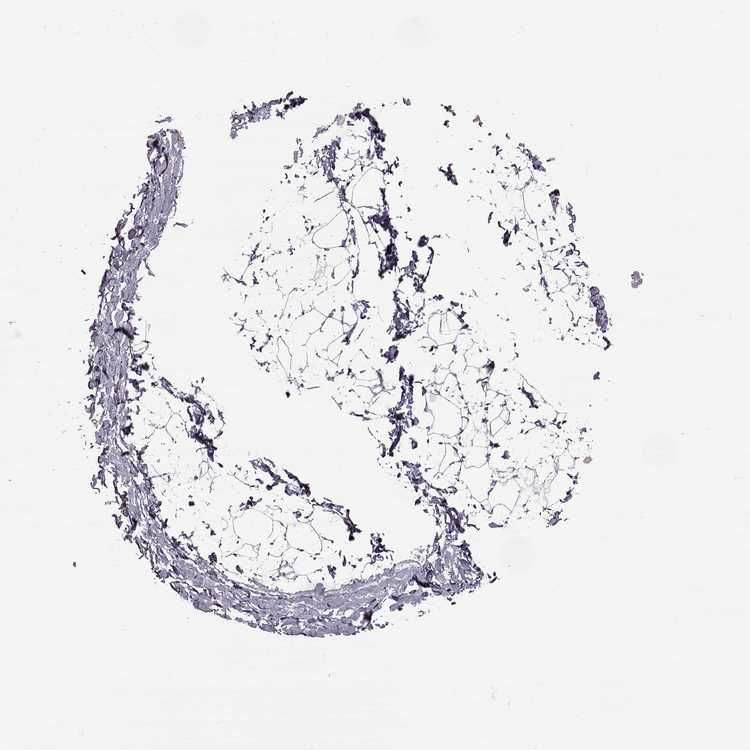

SOFT TISSUE 2 - Antibody stainingi

Antibody staining in the annotated cell types in the current human tissue is reported as not detected, low, medium, or high, based on conventional immunohistochemistry profiling in selected tissues. This score is based on the combination of the staining intensity and fraction of stained cells.

Each image is clickable and will lead to virtual microscopy that enables deeper exploration of all samples and also displays staining intensity scores, fraction scores and subcellular localization as well as patient and tissue information for each sample.

Antibody HPA023908

Fibroblasts Not detected